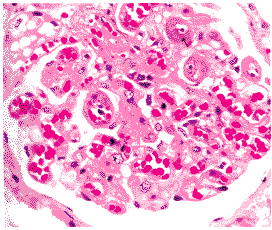

1.黃疸 黃疸為肝內(nèi)膽汁淤積癥最重要的臨床表現(xiàn)。根據(jù)不同疾病呈慢性或急性出現(xiàn),凡黃疸的嚴(yán)重度因疾病和病因不同、病情輕重、病程長短而有差異。可在瘙癢前或后發(fā)生。黃疸的發(fā)生是因肝內(nèi)的毛細(xì)膽管或小膽管因不同原因發(fā)生阻塞,或發(fā)生肝內(nèi)膽汁淤積癥,由于其上方膽管內(nèi)壓力不斷增高、膽管擴(kuò)張,終致膽小管與毛細(xì)膽管破裂,膽汁中的膽紅素反流入血中,從而出現(xiàn)黃疸。

肝內(nèi)膽汁淤積癥癥時(shí)因肝細(xì)胞多不發(fā)生壞死,主要為結(jié)合膽紅素增高,因此與肝性黃疸不同,皮膚多呈暗綠或綠褐色,并可有黑色素沉著,因糞中無膽汁致大便呈灰白色,尿膽原陰性。于黃疸早期往往缺乏明顯的自覺癥狀。慢性膽汁淤積進(jìn)展很慢,開始常見乏力、食欲不振等肝膽疾病癥狀。